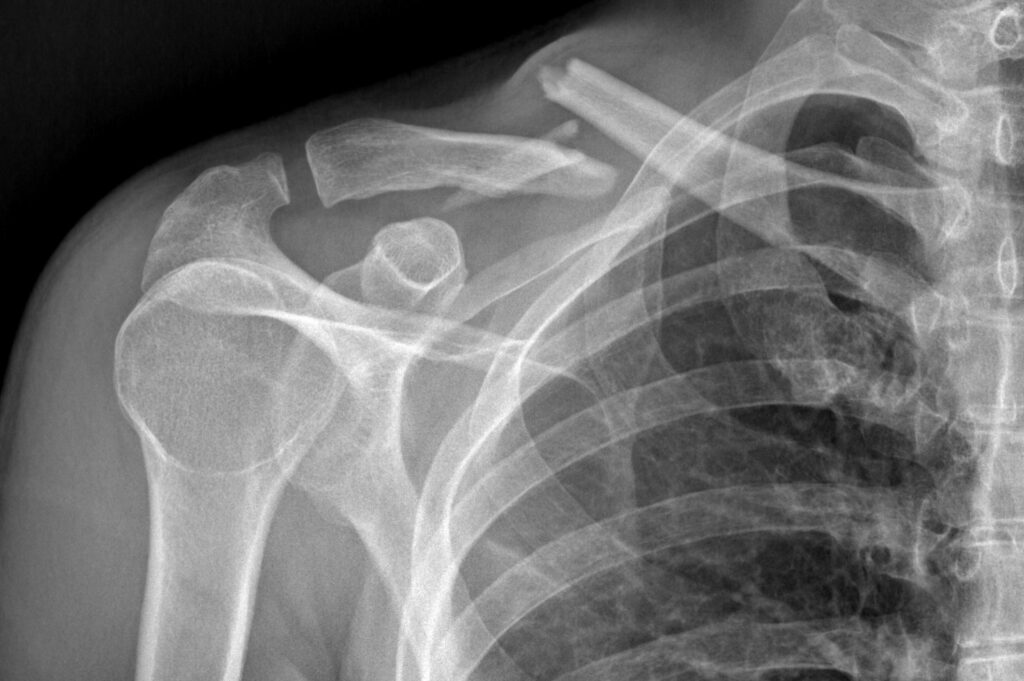

Participé como disertante hablando sobre el manejo de la conminución en fracturas diafisarias de clavicula. Curso completo en YouTube.